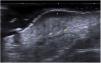

In all the cases, the ultrasound findings showed superficial hypoechogenicity, while 10 of these cases showed hyperechoic regions at the base. Pseudopod projections were a common finding (12/14; 85.7%) (Fig. 1). The color Doppler ultrasound confirmed the presence of hypervascularity in 12 cases (85.7%). In these cases, high-resolution ultrasound suggested the diagnosis, which was ultimately confirmed through histopathological study.

Ultrasound findings of DFSP: Grayscale ultrasound, longitudinal view showing the classic image of a DFSP with an oval mass, poorly defined borders, and a hypoechoic band in the dermis and hypodermis (white arrow). At the base, the lesion is hyperechoic with adjacent borders and pseudopod projections (yellow markers).

Ultrasound allows for the characterization and differentiation of superficial soft tissue masses.3 Diago et al. found 4 patterns of ultrasound invasion of DFSP, with good histopathological correlation. As it happened with our cases, the most common pattern (53.3%) was the presence of an oval hypoechoic mass with pseudopod or digitiform projections and posterior hyperechoic regions (Fig. 1) that correlated with the spread of tumor cells and fibroblasts scattered across the subcutaneous tissue forming the characteristic honeycomb pattern. We should mention that digitiform projections have an asymmetric and unpredictable growth, which makes them highly indicative or pathognomonic. Such structures were found in most of our cases (Fig. 2). The second most common pattern was the oval hypoechoic pattern with pseudopod projections but without posterior hyperechoic regions (20%), which correlated with spread along the subcutaneous septum. Finally, they revealed the presence of a mixed invasive pattern without deep projections (16.7%), or dermal/subcutaneous oval hypoechoic tumors (10%). The ultrasound has sensitivity and specificity rates of 81.8% and 100%, respectively for the detection of deep invasion, with a positive predictive value of 83.3%, which stresses its importance in assessing tumor spread.8